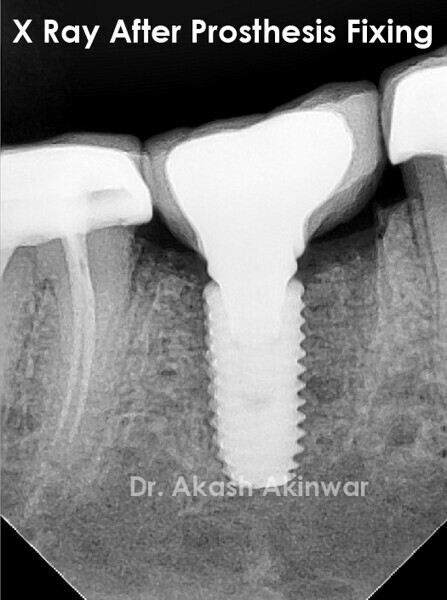

Flapless Single Implant Placement with Screw Retained PFM Prosthesis: Dr Akash Akinwar